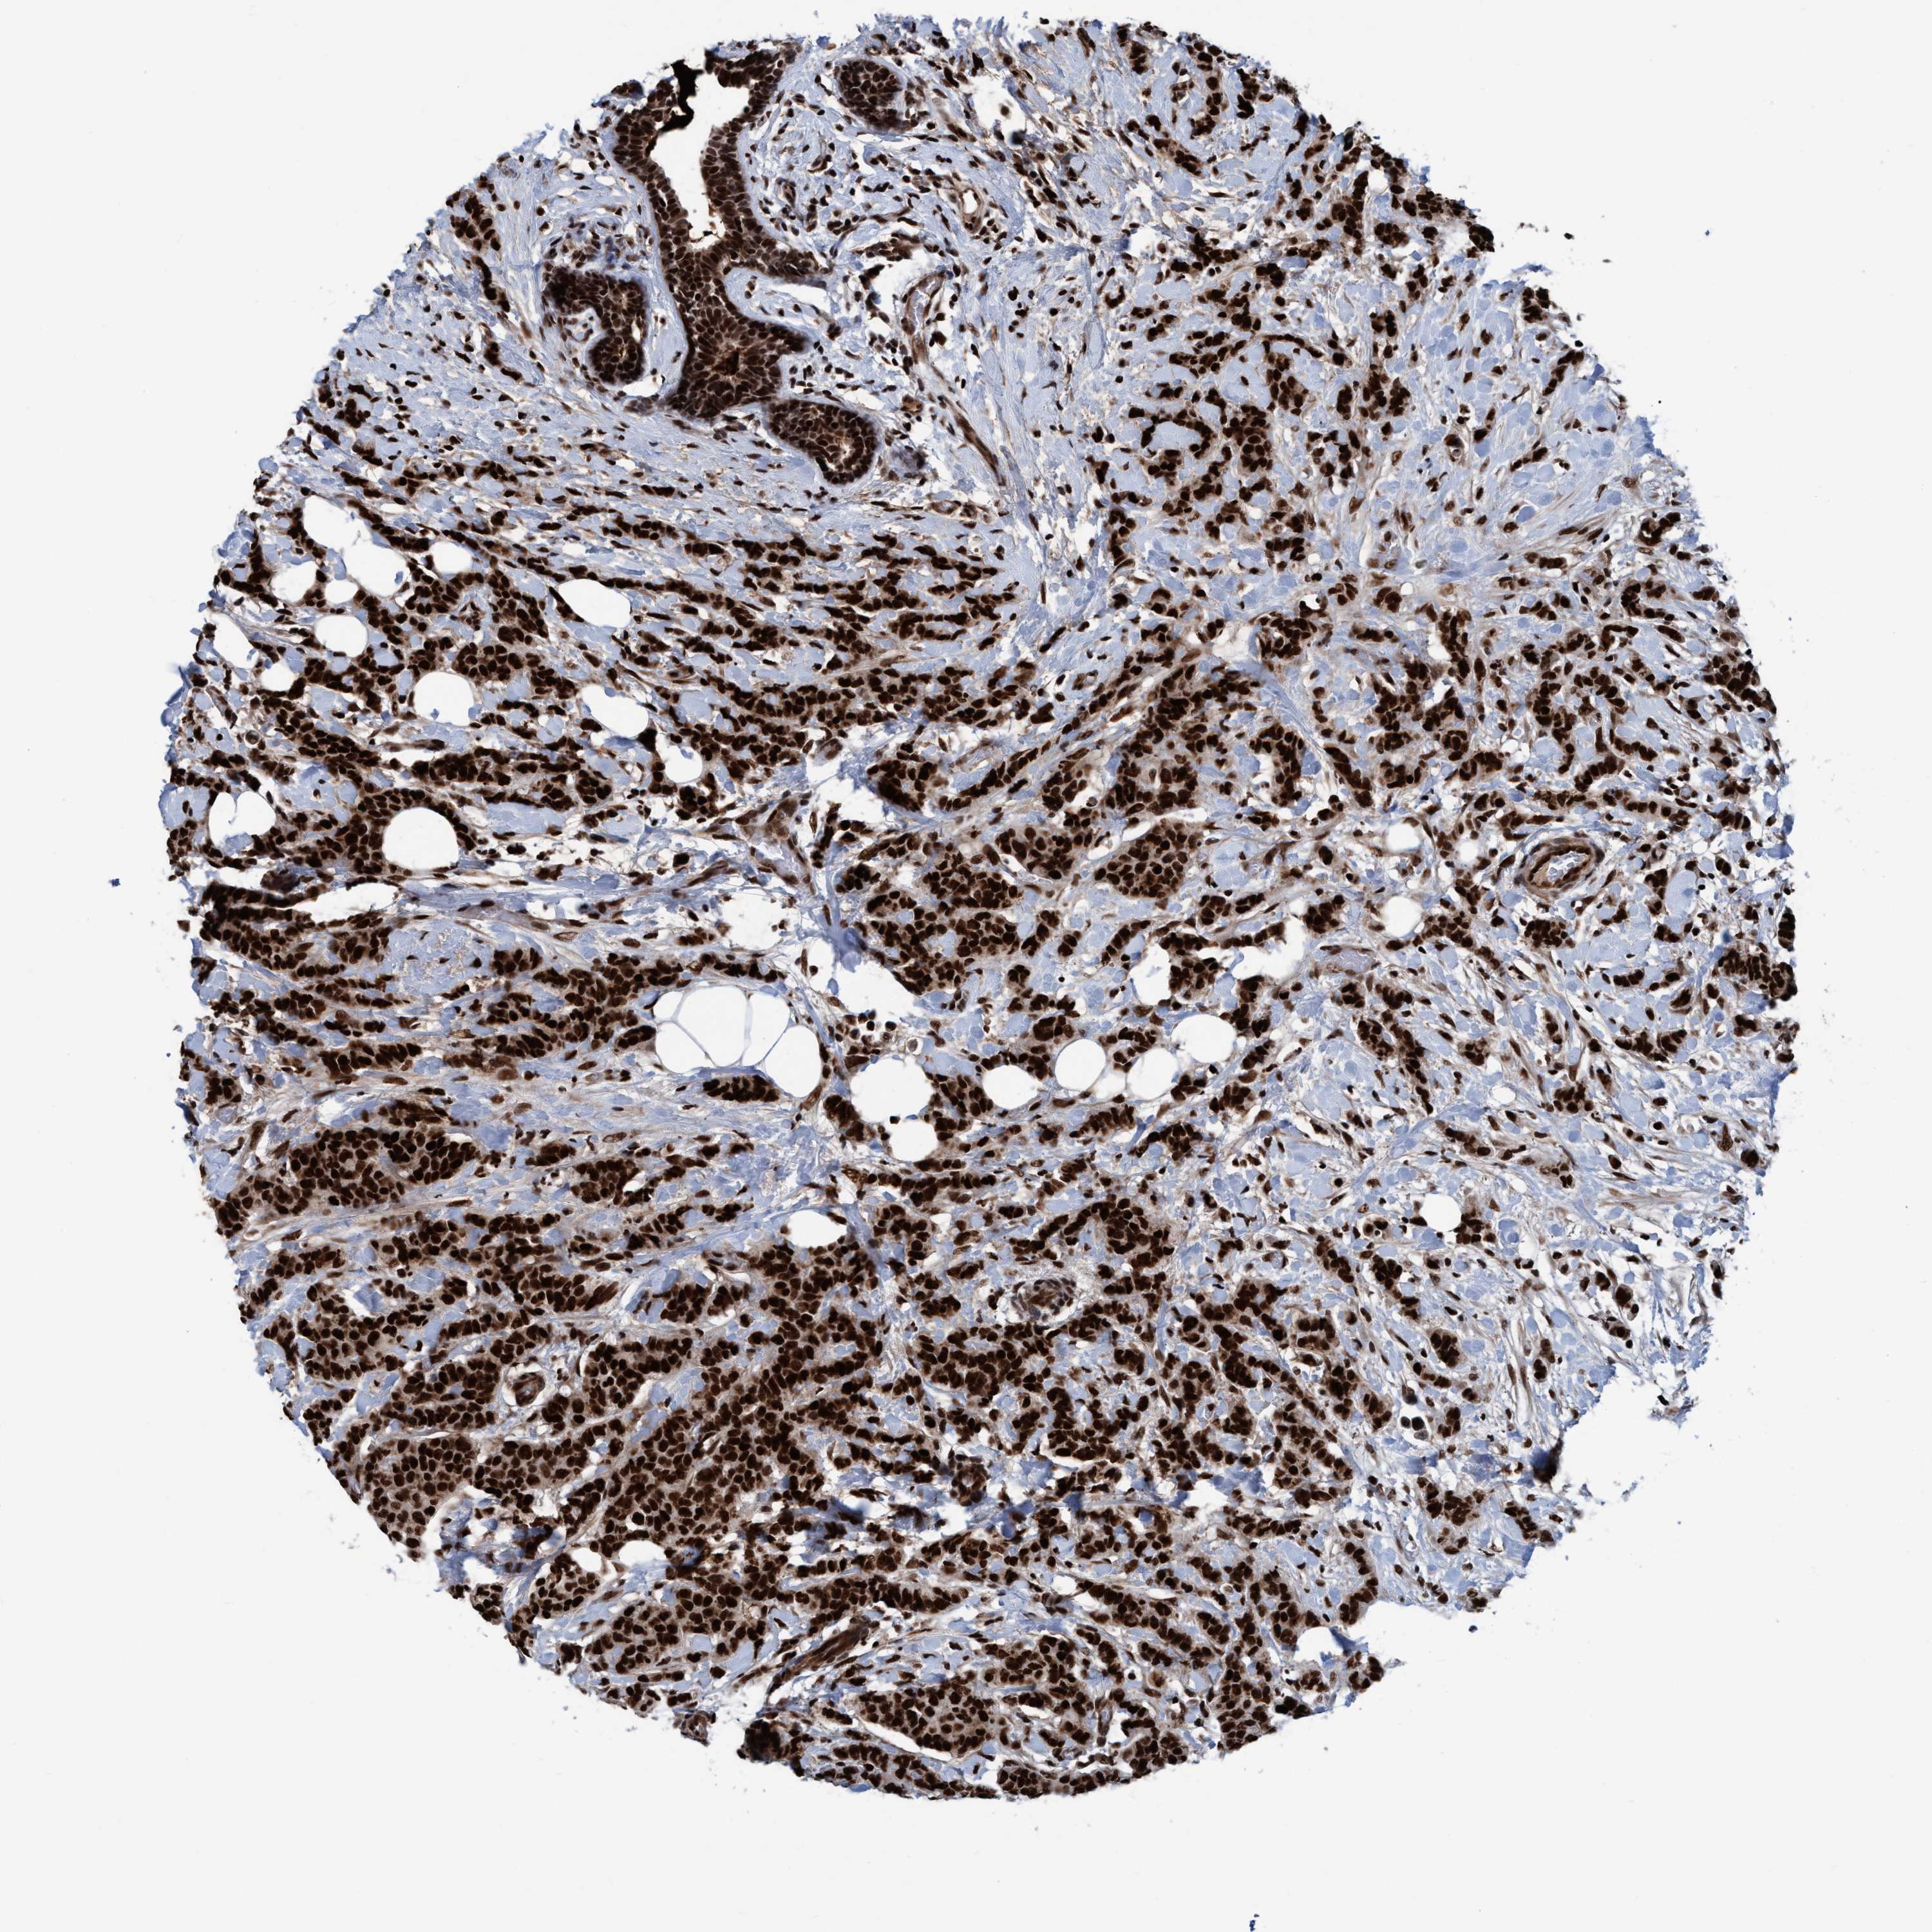

CANCER BREAST CANCER Show tissue menu

BRCA TCGA BRCA VALIDATION PROTEIN EXPRESSION